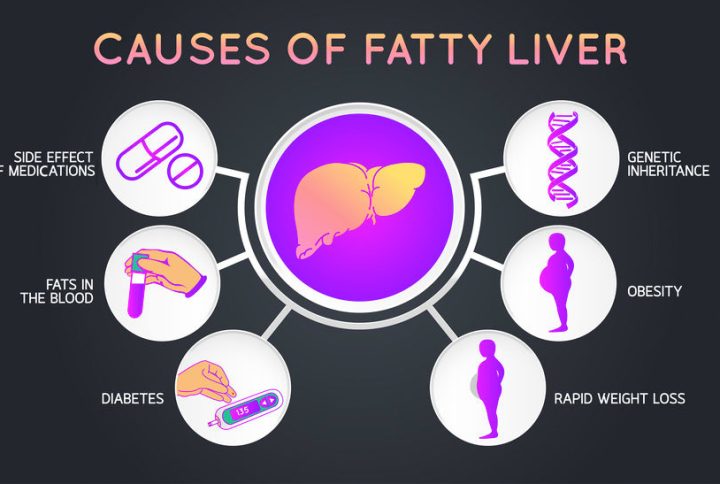

دلایل ایجاد کبد چرب چیست؟

شایعترین علت بروز این بیماری اعتیاد به الکل است. اما درمورد افرادی که الکلی نیستند در بسیاری از موارد پزشکان نمیدانند چه چیزی باعث ایجاد آن میشود.

کارشناسان هنوز به طور دقیق نمیدانند، چرا در برخی افراد دور این اندام چربی تجمعکرده و در برخی دیگر از افراد این عارضه ایجاد نمیشود. اما بهطورکلی میتوان گفت معمولا کبد چرب و سیروز کبدی هر دو به موارد زیر مرتبط هستند و برای جلوگیری از این بیماری باید موارد زیر را کنترل کرد؛

- اضافهوزن یا چاقی

- مقاومت به انسولین

- قند خون بالا که نشاندهنده پیش دیابت یا دیابت نوع ۲ است.

- سطح بالای چربی در خون (بهویژه تری گلیسیرید)

- دیگر علل بیماری کبد چرب چیست؟

- جگر چرب هنگامی ایجاد میشود که بدن چربی زیادی تولید کند، یا به اندازه کافی چربی را دفع نکند. چربی اضافی در سلولهای کبدی ذخیره میشود. در آنجا تجمع مییابد و باعث

- ایجاد این بیماری میشود. این تجمع چربی میتواند در اثر موارد مختلفی ایجاد شود، مانند:

- نوشیدن بیش از حد الکل

- چاقی

- تجمع بیش از حد چربی در اطراف شکم (چاقی شکمی)

- قند خون بالا

- کلسترول بالا

- تری گلیسیرید بالا

- سندرم متابولیک

- مقاومت به انسولین

- دیابت نوع ۲

- کم کاری تیروئید

- کاهش عملکرد هیپوفیز (کم کاری هیپوفیز)

- سندرم تخمدان پلی کیستیک

- مقادیر بالای چربی در خون، به ویژه تری گلیسیرید

- کاهش وزن سریع

- برخی از انواع عفونتها مانند هپاتیت C و اچ آی وی (HIV)

- کمبود آلفا ۱ آنتی تریپسین

- عوارض جانبی برخی از داروها مانند متوترکسات، تاموکسیفن، آمیودارون و داروهای ضدتشنج و ضد صرع، کورتون، استامینوفن (مصرف طولانی مدت) و برخی آنتیبیوتیکها

- بای پس معده

- بارداری

- قرار گرفتن در معرض سموم خاص

- ژنتیک و وجود سابقه خانوادگی

- بیماری التهابی روده (IBS)

- مصرف زیاد کربوهیدرات

- مصرف نوشیدنیهای قندی.